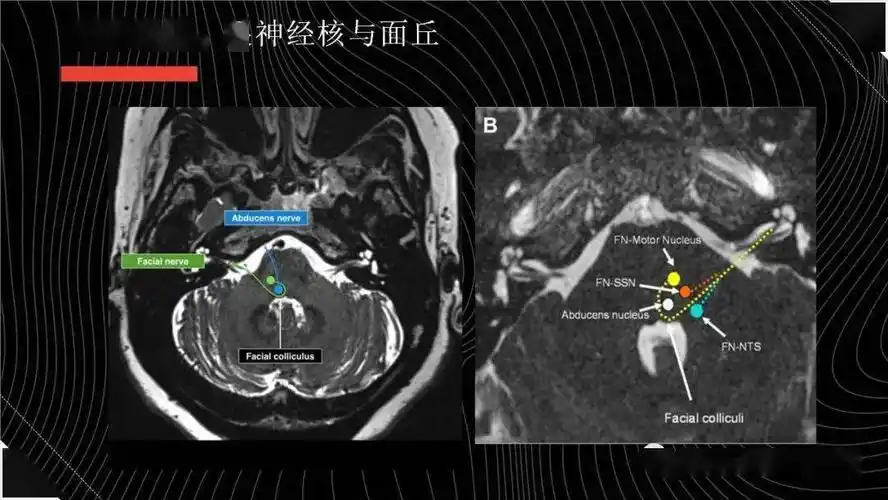

该病典型的 mri 表现为双侧面神经发育不全,在平衡稳态梯度回波序列

12对颅神经连续层面mri解剖